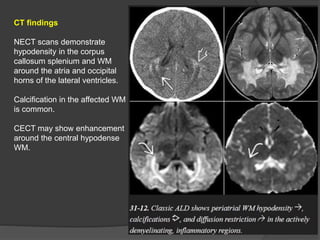

CT findings

NECT scans demonstrate

hypodensity in the corpus

callosum splenium and WM

around the atria and occipital

horns of the lateral ventricles.

Calcification in the affected WM

is common.

CECT may show enhancement

around the central hypodense

WM.

CT findings NECT scansdemonstrate hypodensity in the corpus callosum splenium and WM around the atria and occipital horns of the lateral ventricles. Calcification in the affected WM is common. CECT may show enhancement around the central hypodense WM.